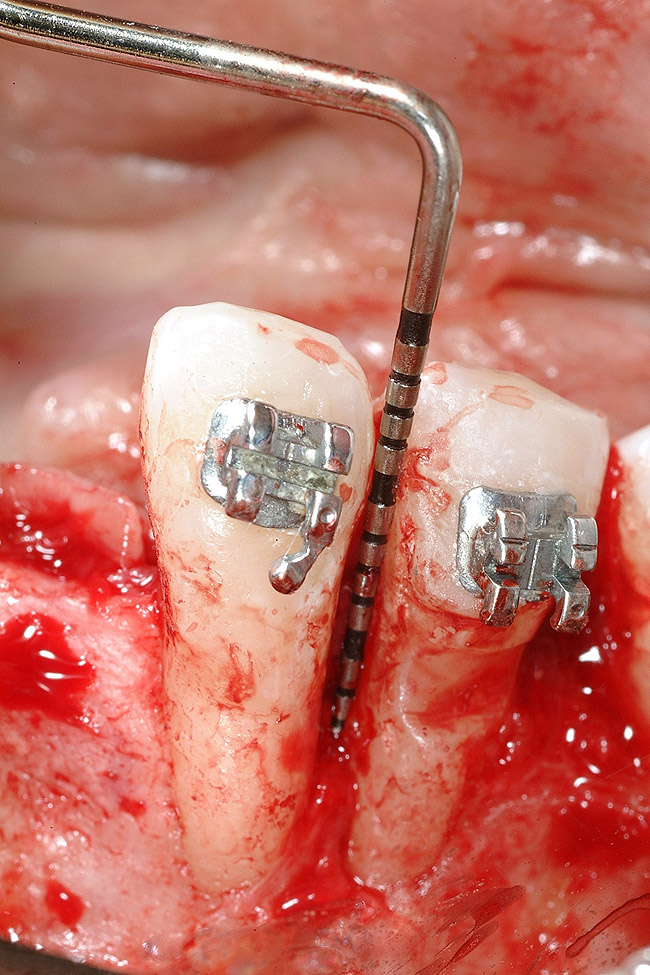

Figure 14  Interproximal bone present at teeth Nos. 21 and 22, postorthodontics.

Figure 14